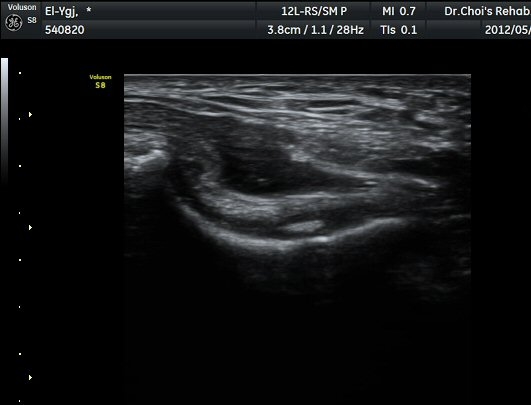

ÁÖ°ü Ⱦ´Ü¸é°Ë»ç¿¡¼­ °üÀý³» ¼ö¾×Àú·ù¿Í ô°ñ½Å°æÀÇ Ç¥ÃþÀ¸·Î ÀüÀ§°¡ °üÂûµÈ´Ù(±×¸² 7).

ÁÖµÎ¿Í È¾´Ü¸é°Ë»ç ¿µ»ó¿¡¼­(»çÁø) ÃÊÀ½ÆÄ À¯µµÇÏ¿¡ °üÀý³» Áֻ縦 ½ÃÇàÇÏ¿´´Ù(µ¿¿µ»ó).